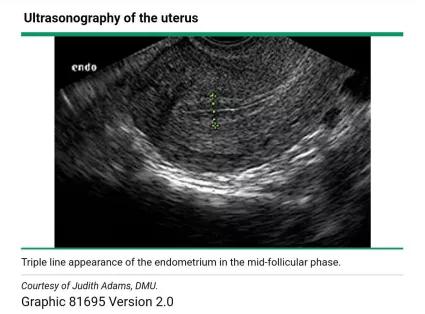

此后,在雌二醇分泌不断增加的影响下,内膜会增生持续整个卵泡期。这种增生在超声上表现为「三线征」,即子宫内膜表现为低回声,而中间和外基底层则表现为强回声亮线(如下图)。

到了卵泡期末期,测量的子宫内膜厚度为8-12mm之间[1]。在月经中期,子宫颈管可被黏液所扩张,表现为宫颈内的无回声带,这被认为是即将排卵的一个征象。